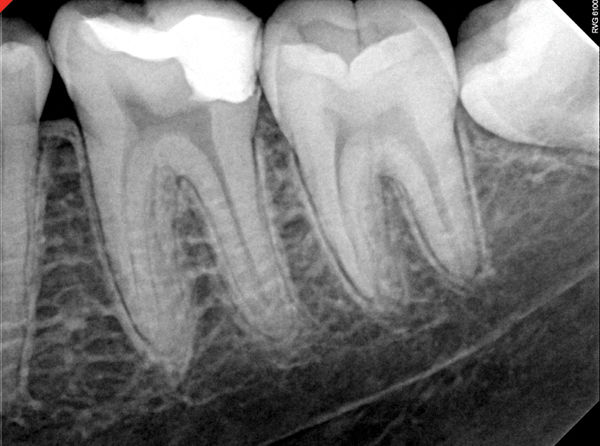

Figure 11. Preoperative radiograph. Courtesy of Dr. Guillaume Jouanny.

Figure 11

Figure 12. Postoperative radiography after full pulpotomy was performed. Courtesy of Dr. Guillaume Jouanny.

Figure 12

Figure 13. Tooth was asymptomatic at 1-year follow-up. Courtesy of Dr. Guillaume Jouanny.

Figure 13

Figure 14. Contralateral tooth at 1-year follow-up. Courtesy of Dr. Guillaume Jouanny.

Figure 14

In this case, the tooth tested vital but showed clinical signs of irreversible pulpitis. Treatment with a full pulpotomy was chosen to improve the chances the remaining pulp would survive and remain healthy. The preoperative radiograph in Figure 11 shows extensive caries in the tooth and a slightly widened apical periodontal ligament. A full pulpotomy was performed using the BC putty (Figure 12). After the putty set, a coronal restoration was placed, and an immediate postoperative radiograph was taken and viewed. At the 1-year follow-up, the tooth was asymptomatic, and the radiograph showed continued root development (Figure 13), a healthy apical periodontium, and, importantly, no calcifications in the remaining pulp (as is often seen with a calcium hydroxide therapy). A radiograph taken of the contra-lateral tooth showed similar root development (Figure 14).